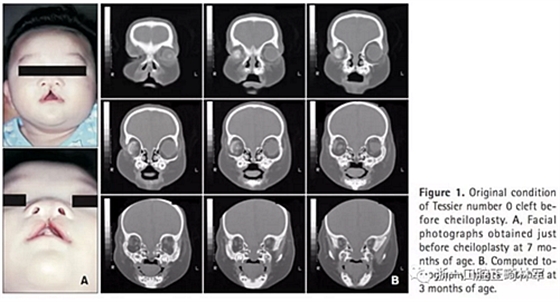

患者信息(圖1):

5歲Tessier0號面裂伴右側(cè)小眼畸形。病史如下:1月起右側(cè)佩戴義眼,7月行唇裂修復(fù)術(shù),1歲11月時行腭成形術(shù)(V-Y),7歲7月時行髂骨移植術(shù),8歲10月時摘除畸形眼球后植入人工植體,10歲1月時行額部懸吊及各項眼瞼整形手術(shù)。

臨床檢查及診斷(圖2,3;表1):

患者表現(xiàn)為面中結(jié)構(gòu)過寬;口內(nèi)檢查提示前牙開合(覆合-2.5mm)及上牙弓窄縮。全景X線片顯示先天性缺失上頜乳中切牙及恒中切牙,前頜骨骨缺損和上頜左側(cè)乳切牙的萌發(fā)。頭側(cè)提示上下頜骨后縮(SNA,76.3°;SNB,74.8°;A to N,−3.9mm; Pog to N,−10.0mm) ,ANB角正常(1.5°),下頜平面角大(FMA,31.5°),下頜角大(125.4°)。上頜乳側(cè)切牙及下頜乳中切牙舌傾(primary U2 to SN,89.7°;primary IMPA,75.6°)。